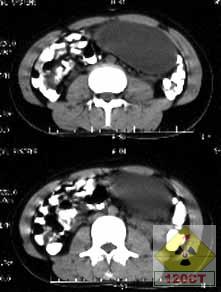

(1)典型的CT徵象為密度不均的囊性腫塊,單側或雙側性。

(2)囊壁厚薄不均,邊緣光整。

(3)內含脂肪密度影和發育不全的骨骼及牙齒,也可見自囊壁突起的實體性結節影。如囊內同時含有脂肪和液體,則可見到上脂肪下液體的液-脂界面,並可隨體位變動而改變位置。

(4)如為皮樣囊腫時,CT僅表現為含液體的囊性占位,但囊壁可有蛋殼樣鈣化。

(5)惡性畸胎瘤侵及鄰近組織,表現為腫瘤與周圍器官的脂肪層消失;腫瘤侵及膀胱、盆腔肌肉或腸管,則表現為與他們之間的分界不清。